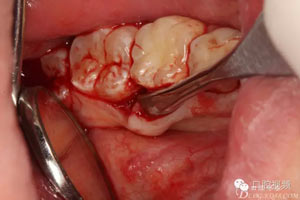

圖7.通過CBCT準(zhǔn)確定位,暴露35部分牙冠。

圖8.繼續(xù)去骨、暴露整個35牙冠。注意牽拉力度。